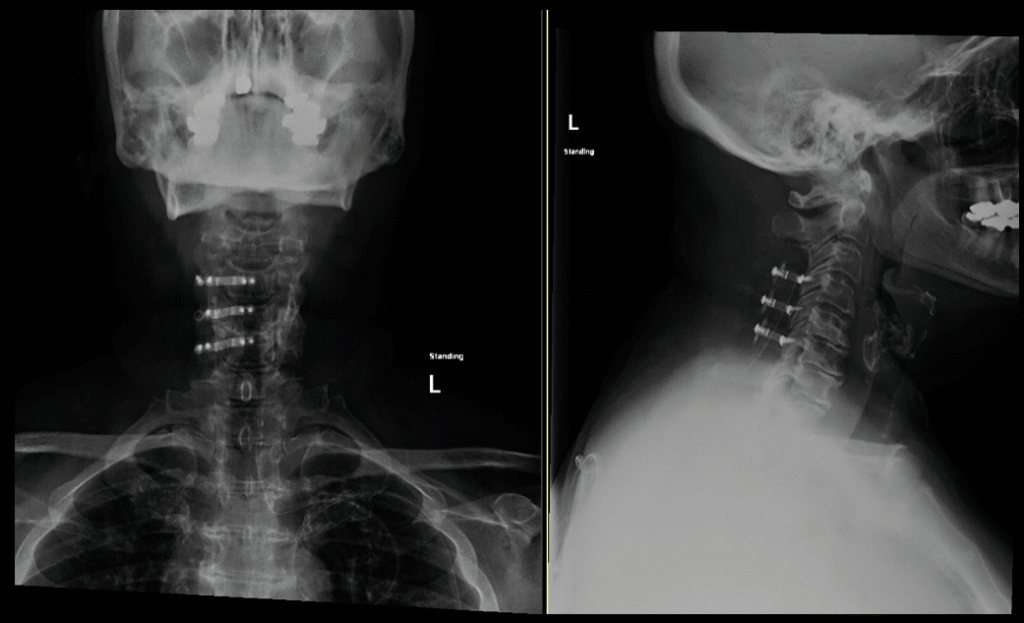

C1-2 fusion

Posterior Cervical Spine Surgeries

Posterior Cervical Fusion